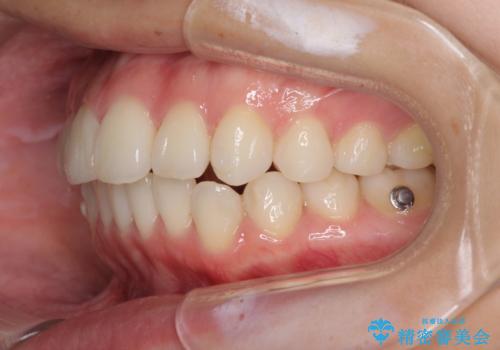

- デコボコと飛び出した前歯を治したいとのことで来院された患者様です。

ゴムかけを活用して上顎歯列全体を後方移動し、IPR(歯と歯の間を削る)によってデコボコが解消するように設計し、インビザラインにより治療を行うこととしました。

後方移動に際し、上下顎の親知らずは4本とも抜歯することとしました。

毎日しっかりと装着してくださったので、概ねシミュレーション通りに歯を移動させることができました。

治療前には接触することのなかった上下の前歯が接触するようになり、食事の際前歯でものをかみ切れるようになりました。

気にしていた口元の印象が改善され、患者様には大変満足していただきました。